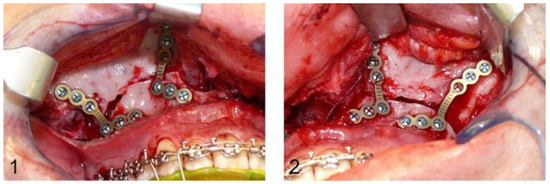

After Le Fort I osteotomy, the ascending mandibular branch and the mandibular angle are exposed and mandibulomaxillary fixation with wire ligatures is followed. An L-shaped titanium plate with four osteosynthesis screws is placed bilaterally to fix the ascending mandibular branch and the crista zygomaticoalveolaris cranial to the pre-osteotomised maxilla in order to complete the osteotomy. After removal of the fixation plates, the maxilla can be freely mobilised and adjusted with the CAD/CAM intermediate splint, following mandibulomaxillary fixation over the orthodontic arches. The previously removed L-shaped fixation plates are reinserted bilaterally in the original position using the former drill holes, and the planned maxillary position is transferred to the surgical site via the CAD/CAM splint. The conventional osteosynthesis starts with a hand-bent L-shaped plate on each side paranasally. The fixation plates are then removed again and the definitive, conventional osteosynthesis in the region of the crista zygomaticoalveolaris is also performed with a hand-bent L-shaped plate (DePuy Synthes®, Matrix ORTHOGNATHICTM, Warsaw, IN, USA) and monocortical osteosynthesis screws with a diameter of 1.85 mm and a typical length of 4 mm bilaterally (Figure 1).

Figure 1.

Image (1,2): Intraoperative situs after definitive conventional osteosynthesis of the maxilla with L-shaped osteosynthesis plates paranasally and in the region of the crista zygomaticoalveolaris.